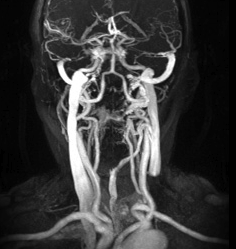

Afterwards, I get to see some images from the MRI on his computer screen. He looks at me rather quizzically and says he can’t imagine that this would be a fun monthly adventure for me.